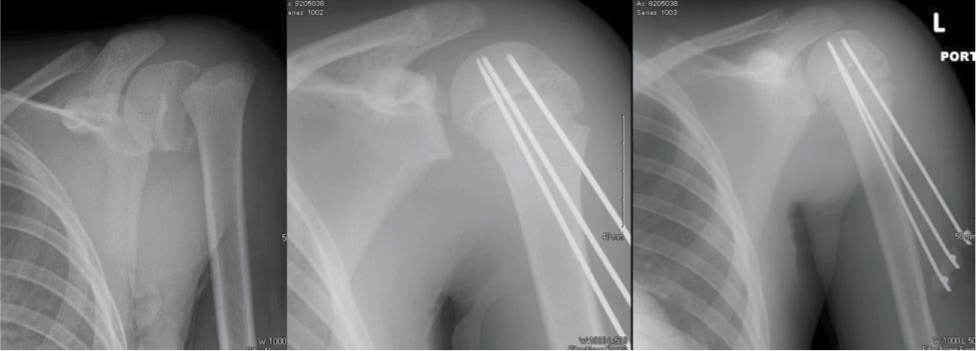

Figure 10. A 13-year-old football player, with Division 1 football skills and aspirations, has a significantly displaced proximal humerus fracture treated with closed reduction and pin fixation.

jposna2023703_fig10.jpg

If smooth pin fixation is the final planned construct, we will use 3-4 pins that are 2.0 to 2.4 mm in diameter (Figure 10).

Definitive Fixation with Smooth Pins

With the fracture reduced, the next step is to place wires to either definitively stabilize the fracture or serve as guide pins for cannulated screws. Percutaneous pin fixation is cheaper, and because these fractures heal quickly, they can be removed at 3-4 weeks before pin tract infection can become problematic. When using this method, we use smooth pins that can be removed in clinic, and we have not found the need to use terminally threaded pins. In the senior author’s opinion, we have found that placing these wires is a challenging task. The humeral shaft is relatively narrow compared to the surrounding shoulder girdle which is usually swollen from the trauma. Wires are introduced from distal below the path of axillary nerve and driven from the shaft into the humeral head. The trajectory required to fix both bones requires an oblique entry into hard cortical bone. The entry angle needed for pins to traverse the fracture can prove difficult, as the pins will tend to skive as a more distal-to-proximal trajectory is pursued. Drilling through a drill guide to more firmly anchor the wire, first with the pin perpendicular to the cortex and then slowly angling more proximal once small amount of purchase is obtained, can limit this pitfall (Figures 8 and 9).